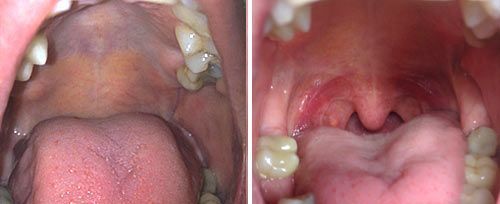

NightLase® is a patented, fast, non-invasive and friendly way of increasing the quality of your sleep. NightLase® lessens the effects of sleep apnea and decreases the amplitude of snoring through the use of gentle, superficial Er:YAG laser light. No anesthesia is used in this treatment.

During NightLase® treatment, the laser light heats the tissue, causing tightening of the tissue which leads to an attenuation of the sound of the patients snoring and a lessening of the effects of sleep apnea. The procedure is performed in two simple steps: